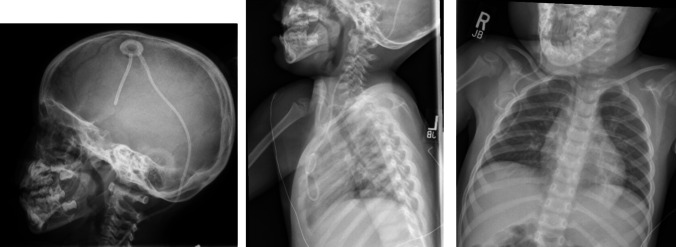

Introduction: Neuronal ceroid lipofuscinosis type 2 (CLN2) is a genetic disease caused by deficiency of the enzyme tripeptidyl peptidase 1 (TPP1), resulting in seizures, vision/cognitive decline, and early death. Cerliponase alfa is an enzyme replacement therapy approved as treatment for CLN2 disease, administered by intracerebroventricular infusion via a surgically implanted device. Maintaining sterility for prolonged scalp-based infusions can be difficult in children and damage devices. We report the development of a technique connecting the intraventricular device and catheter to a chest port to mitigate some of these challenges.

Methods: We describe a seven-patient cohort who underwent implantation of our modified infusion system connecting a ventricular catheter distally to a central venous access device (CVAD) port implanted in the anterior chest.

Results: Between March 2019 and April 2024, seven (n = 7) patients aged 2-19 years underwent the placement of this system or had an old device converted to a CVAD port system. None of our patients has experienced significant access issues, infection, or required revision since implantation.

Conclusions: The use of an intraventricular access device connected to a CVAD allows for safe and efficacious long-term infusion of cerliponase alfa therapy and provides a more stable and well-tolerated alternative to scalp-based infusions.